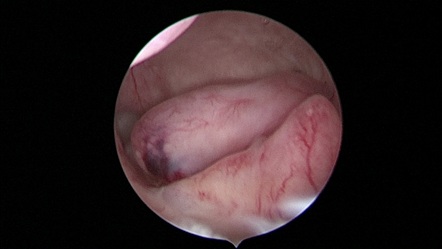

Hysteroscopy showing Submucus Fibroid in Uteruine Cavity.

Three-Dimensional Ultrasonography (3D USG) in comparison to hysteroscopy is less invasive, cheaper, easily accepted by most patients and does not require much training. In most cases an endometrial polyp can be differentiated from the submucous fibroid based on the imaging characteristics. The polyps are typically round in shape, smooth in outline, and are generally echogenic, compared to the endometrium or are isoechoic to it. The underlying endometrial-myometrial interface is preserved (Figure 5). Moreover the presence of a vascular pedicle has a positive predictive value of up to 81.3%. Fibroids are more inhomogeneous, hypoechoic, and there is a loss of endometrial-myometrial interface. The percentage of the intra cavitary portions of the submucous fibroids i.e., grade of submucous myoma can be assessed on 3D USG by the degree of distortion caused by it (Picture 6).